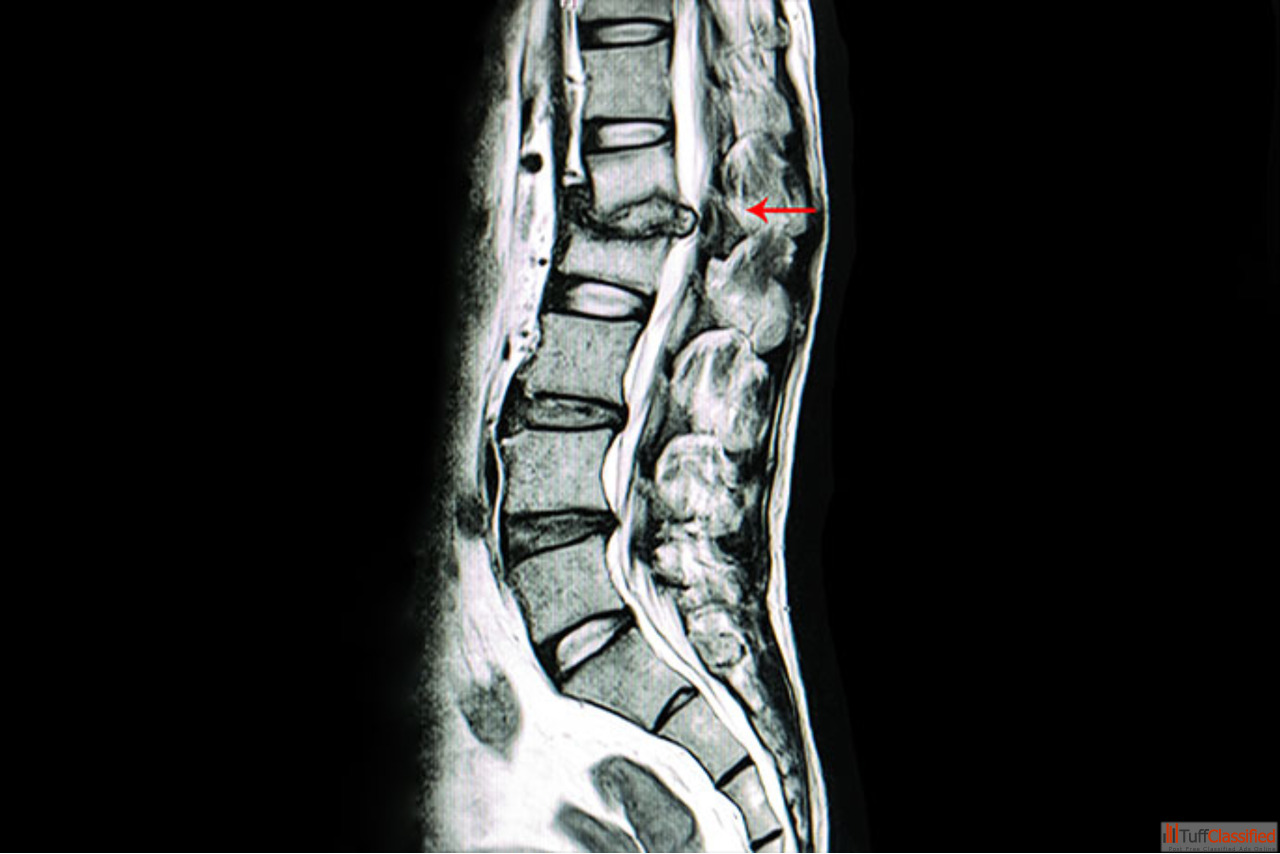

Get expert Tuberculosis Spine Surgery in Vizag from Dr. B. Leela Prasad, a trusted spine surgeon known for advanced diagnosis and minimally invasive corrective procedures. His treatment approach focuses on removing infected tissue, stabilizing the spine, and preserving maximum mobility while ensuring faster healing and reduced complications.

If you are experiencing spinal pain, weakness, or neurological symptoms due to TB of the spine, Dr. Leela Prasad provides precise, evidence-based care to restore stability and prevent further deformity. Book your consultation today for safe and effective TB spine treatment in Vizag.